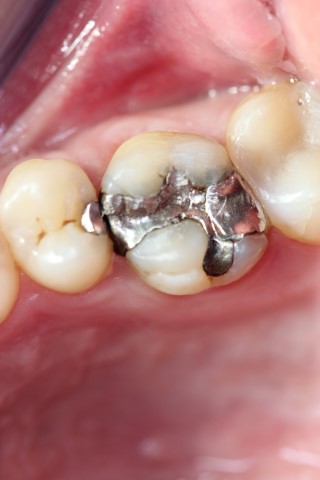

Gli intarsi dentali vengono proposti quando abbiamo ancora tessuto dentale sufficiente ad evitare una corona, ma troppo esiguo per procedere ad una semplice otturazione.

Il dente per essere recuperato viene sottoposto ad una particolare preparazione, successivamente alla quale si rileva un’impronta con materiali specifici (polieteri) ed inviata al laboratorio odontotecnico dove a seconda dei casi si decide alla realizzazione dell’intarsio in ceramica, di-silicato o composito.